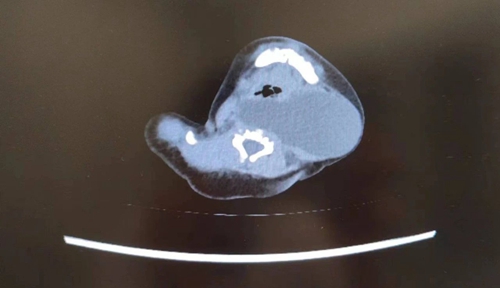

胎兒醫(yī)學(xué)中心及時(shí)邀請(qǐng)小兒外科專家會(huì)診,專家們根據(jù)囊腫位置、形態(tài),進(jìn)一步確定包塊為腮裂囊腫。腮裂囊腫是一種因胚胎發(fā)育過程中鰓裂與鰓弓未完全融合或完全未融合所致的先天性鰓源性囊性病變。常見于10~40歲,胎兒期罕見。

隨著孕周增加,胎兒頸部包塊逐漸增大。孕39周時(shí),超聲提示囊腫增大至42*39.9mm,為確保母嬰安全,胎兒醫(yī)學(xué)中心、產(chǎn)科專家經(jīng)過分析決定為孕婦實(shí)行剖宮產(chǎn)。醫(yī)護(hù)團(tuán)隊(duì)反復(fù)評(píng)估和討論,制定了周密的手術(shù)計(jì)劃,芳芳順利分娩一名女嬰。寶寶出生后,專家檢查發(fā)現(xiàn)囊腫位于患兒咽后及左側(cè)動(dòng)脈間隙,可能流膿、感染,且腫物越長越大,可能壓迫寶寶氣管,手術(shù)風(fēng)險(xiǎn)和麻醉風(fēng)險(xiǎn)都將進(jìn)一步提升,必須及早手術(shù)。

時(shí)間緊迫,越早手術(shù)效果越好。寶寶出生第2天,救治團(tuán)隊(duì)為患兒進(jìn)行全麻下置管引流+超聲引導(dǎo)經(jīng)皮硬化術(shù),引流膿液約80ml,成功清除囊腫。